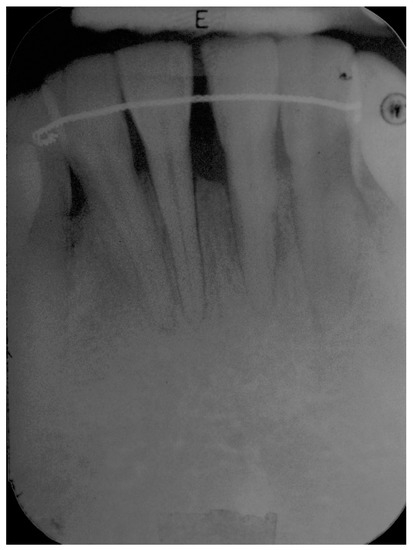

5. Materials and Methods

6. Results